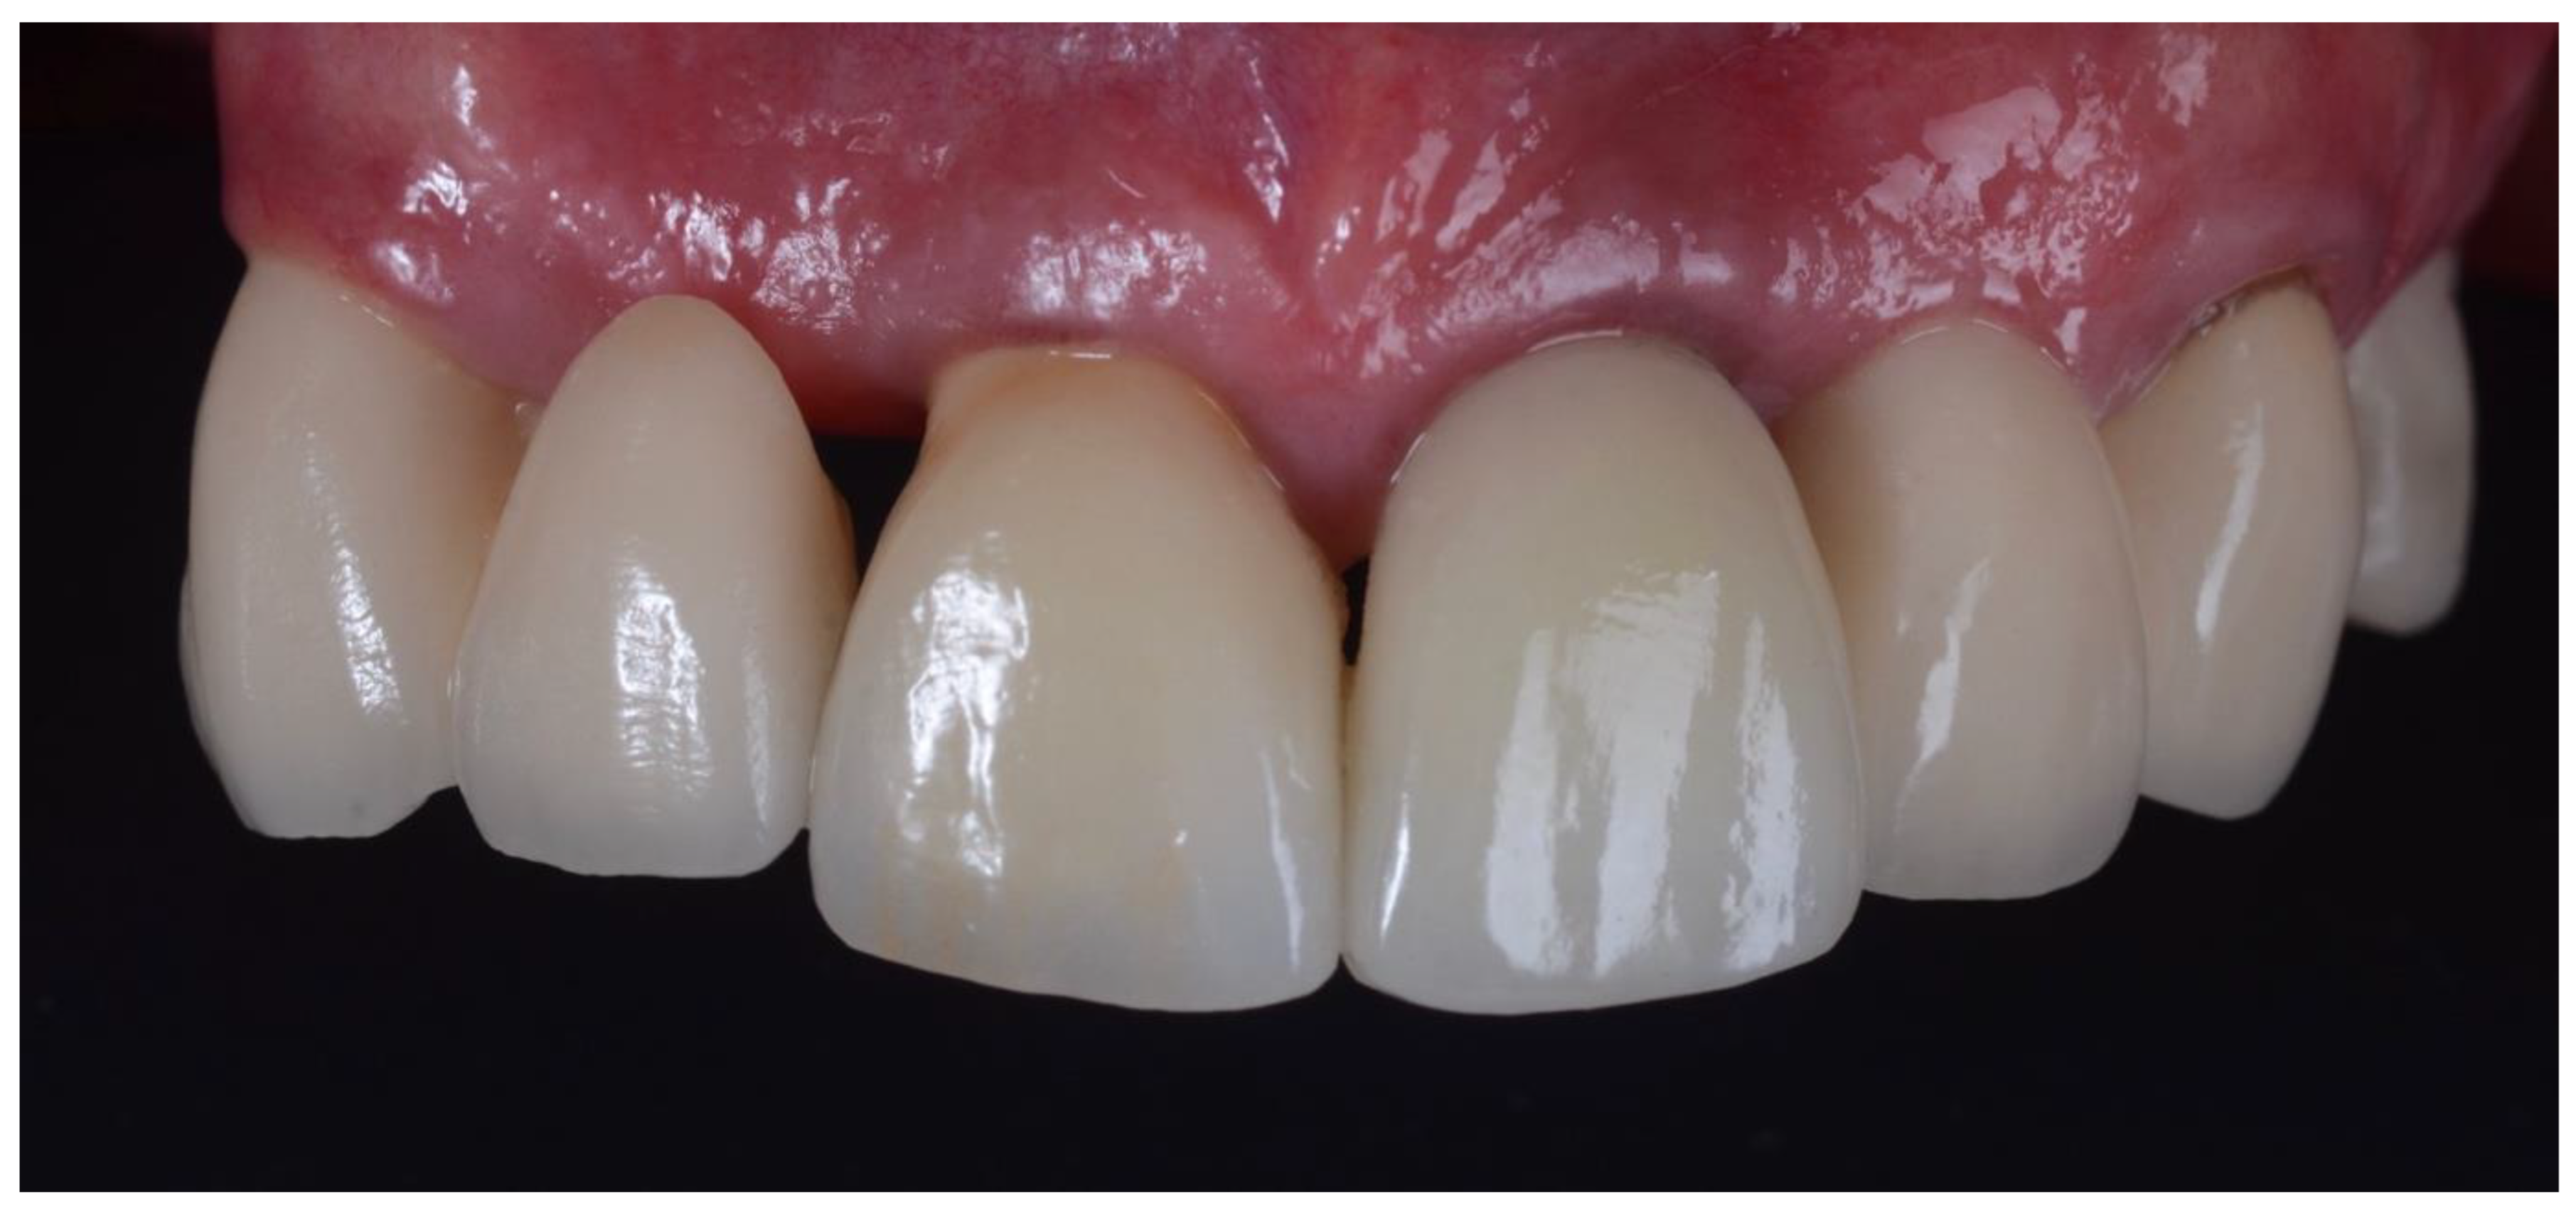

2.1. Surgical Technique